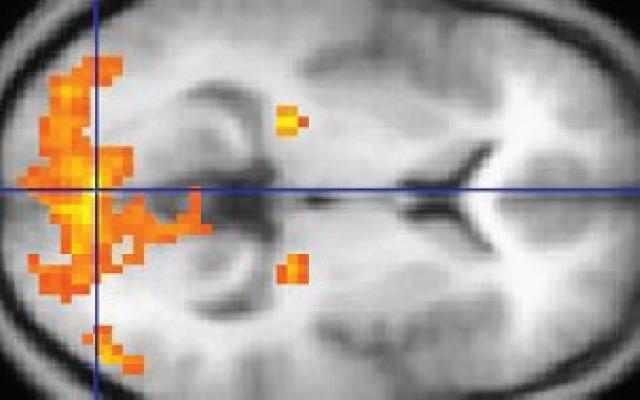

Naast MRI als beeldvormend onderzoek hebben we tegenwoordig ook de beschikking over functionele MRI (fMRI)

Hiermee kan activiteit in verschillende hersengebieden in beeld gebracht worden.

Sinds de introductie van fMRI, wordt deze techniek veel gebruikt in de preoperatieve analyse van hersentumoren.

Ook emotionele centra kunnen in beeld worden gebracht.

Dit artikel bespreekt enkele toepassingen en beperkingen van fMRI bij het bestuderen van emoties.